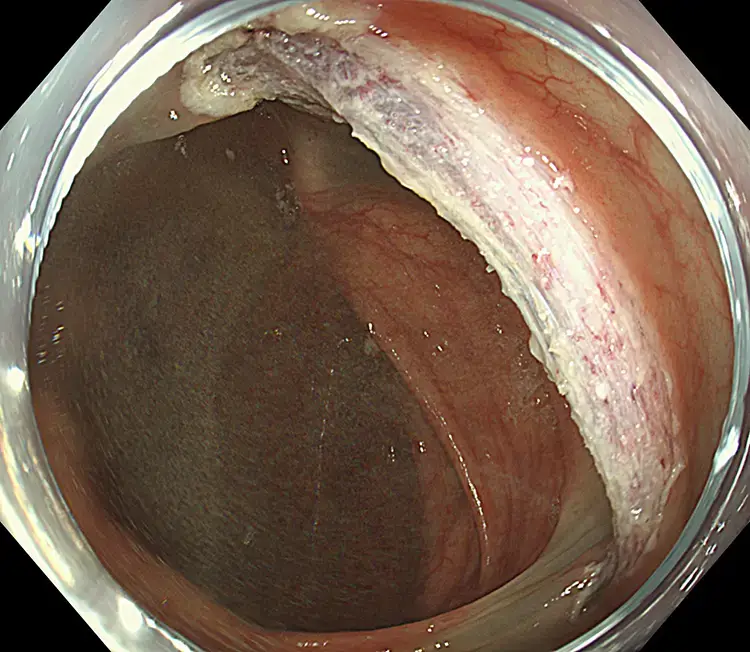

Endoscopic Mucosal Resection (EMR)

Endoscopic Mucosal Resection (EMR) is performed during colonoscopy. Fluid is gently injected beneath the polyp to lift it away from the bowel wall. A fine wire loop (snare) is then placed around the polyp and removed with a small electric current, which also seals blood vessels to reduce bleeding. Larger polyps may be removed in pieces. All removed tissue is collected and sent to the laboratory for analysis.